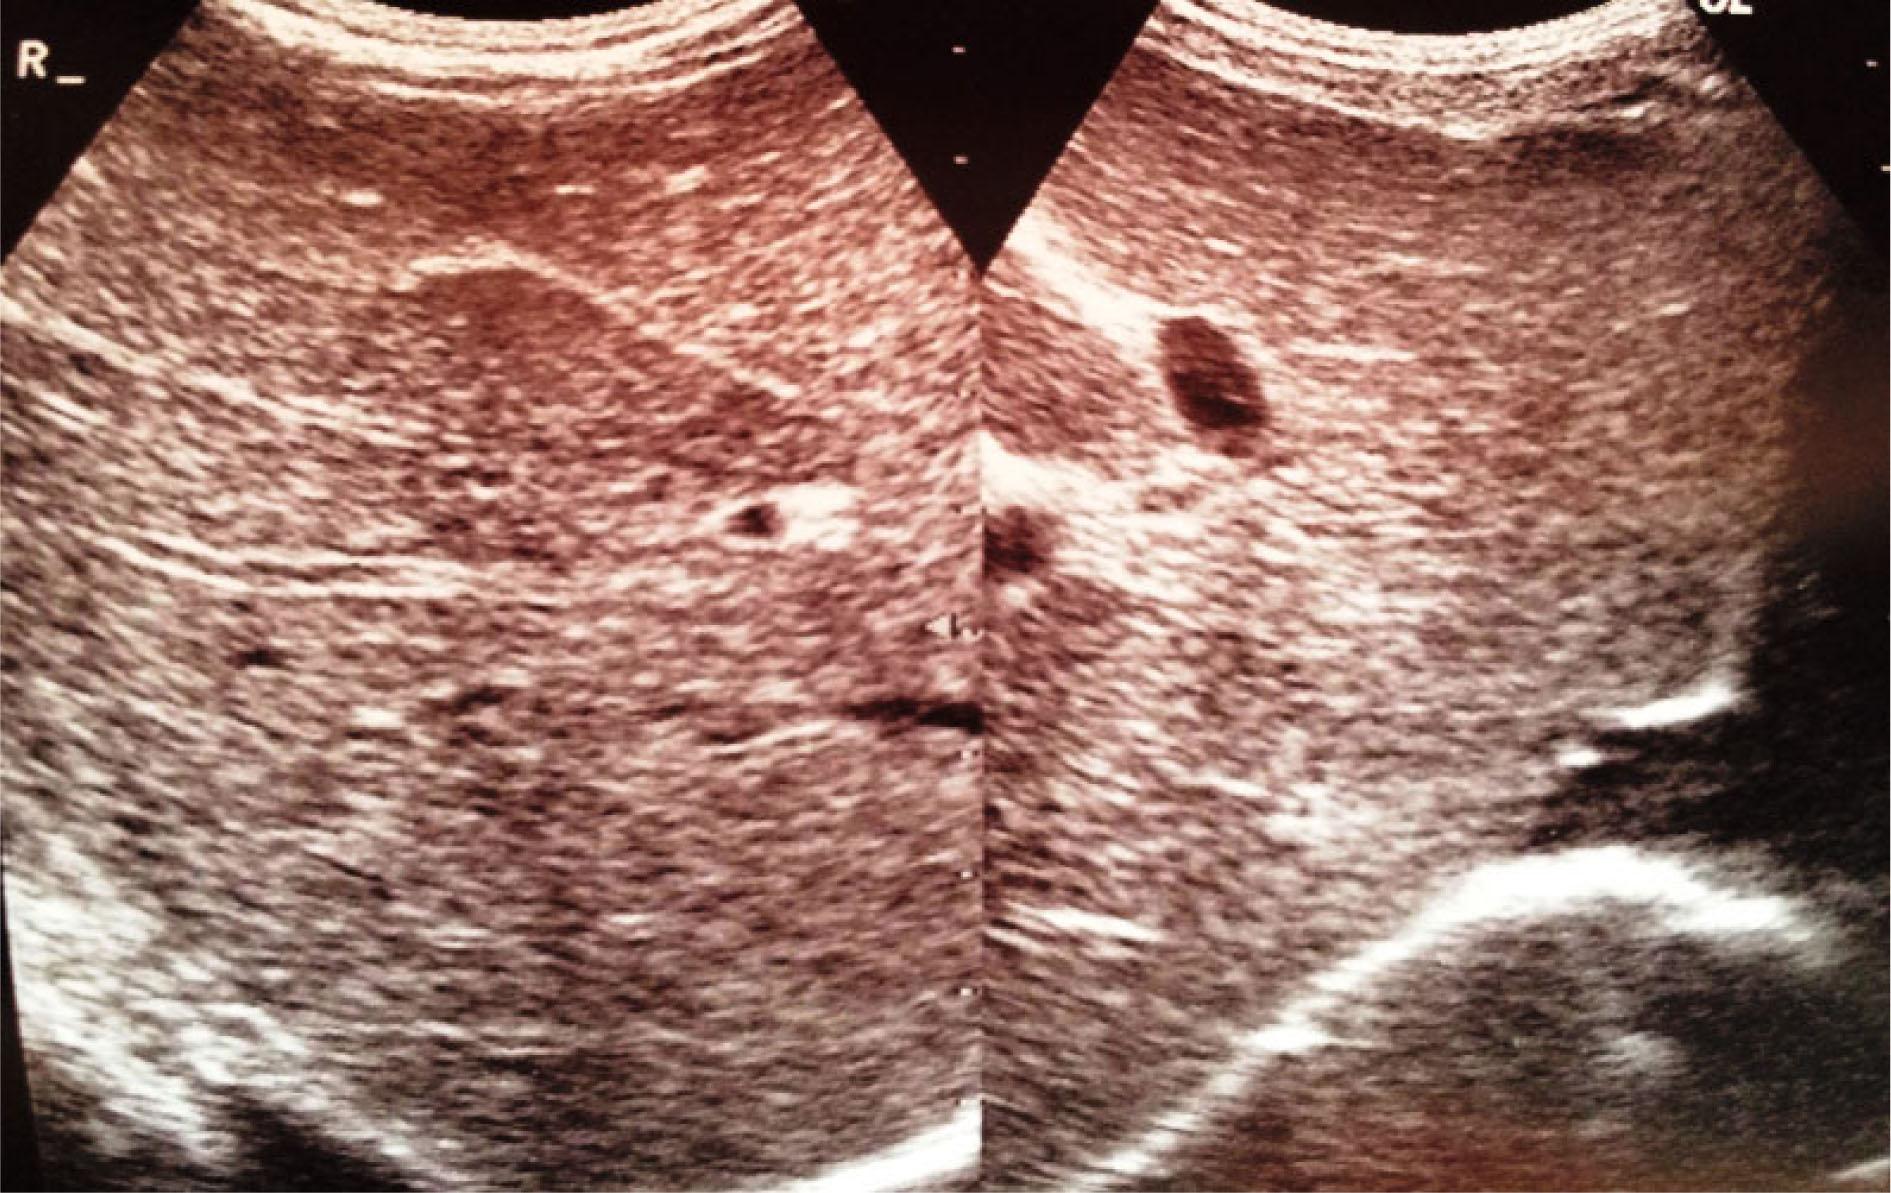

Fig. 2